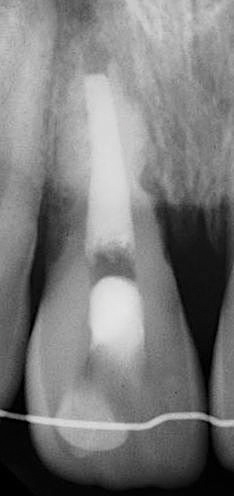

Following the induction of bleeding, a resorbable collagen matrix is placed over the blood clot. Next, a bioceramic material is placed directly over the collagen matrix, a glass ionomer is placed over the bioceramic material, and a final composite or amalgam restoration is placed over the glass ionomer. Once the restoration is complete, a final radiograph is taken (Figure 3 and Figure 4), and the patient is put on 6-month recall for up to 3 years, as dictated by the healing process (Figure 5).25

(3.) Preoperative radiograph of necrotic permanent tooth No. 29.

Figure 3